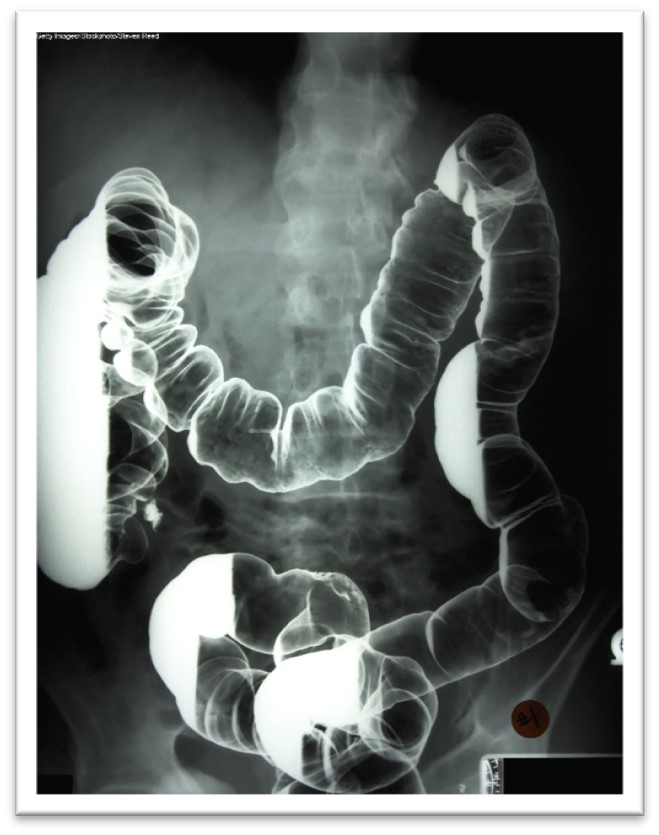

Barium X-rays

Barium x-rays are used to diagnose underlying pathology within the GI tract, including ulcers, inflammation, tumors, hernias, or strictures. Barium is a white, chalk-like powder mixed with water to create a liquid that is either ingested by the patient or administered via an enema. The barium coats the lining of the GI tract, providing visualization of the walls of the esophagus, stomach, and intestines. This allows radiologists to evaluate these structures' contour, shape, size, and patency to identify any underlying pathology. After the barium is administered, fluoroscopy allows the radiologist to see the movement of the barium through the GI tract. There are three barium x-ray procedures: the barium enema or lower GI series, the barium small-bowel meal, and the barium swallow or upper GI series. Barium x-ray tests are typically performed as an outpatient procedure, and each test's defining features and details are described in Table 4 (Gotfried, 2023; Murphy, 2023a). More information regarding barium is discussed later in this module.

Table 4

Barium X-ray Procedures

Procedure | Description |

Barium enema (lower GI series) |

|

Barium small-bowel follow through |

Barium swallow (upper GI series) |

(Gotfried, 2023; Murphy, 2023a)